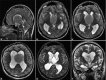

Background: Colloid cysts are usually located at the rostral part of the third ventricle in proximity to the foramina of Monro. Some third ventricular colloid cysts, however, attain large sizes, reach a very high distance above the roof of the third ventricle, and pose some challenges during endoscopic excision. These features led to the speculation that for such a pattern of growth to take place, the points of origin of these cysts should be at areas away from the foramina of Monro at which some anatomical "windows" exist that are devoid of compact, closely apposed forniceal structures.

Results: Colloid cysts may grow vertically up past the roof of the third ventricle through anatomical windows devoid of the mechanical restraint of the forniceal structures.

Conclusion: Some anatomical variations of the forniceal structures may allow unusually large sizes and superior vector of growth of a retro- or post-foraminal colloid cyst. Careful preoperative planning and knowledge of the pertinent pathoanatomy of these cysts before endoscopic excision is very important to avoid complications.